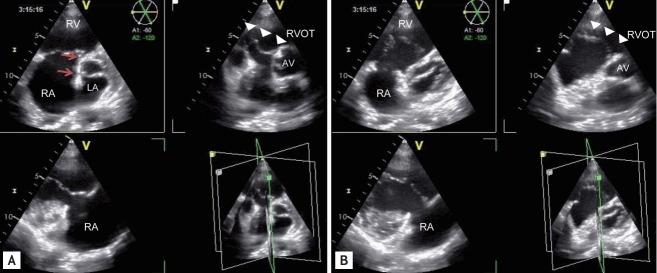

Congenital heart disease (CHD) is now more common in adults than in children due to improvements in fetal echo, neonatal and pediatric care, and surgical techniques leading to dramatically increased survivability into adulthood. Adult patients with CHD, regardless of prior cardiac surgery, experience further cardiac problems or therapeutic challenges; therefore, a non-invasive, easily accessible echocardiographic examination is an essential follow-up tool. Among echocardiographic modalities, three-dimensional (3D) echocardiography provides better delineation of spatial relationships in complex cardiac geometries and more accurate volumetric information without geometric assumptions. For atrial septal defects, an en face view of the tissue defect allows better decisions on device closure. For tricuspid valve malformations, an en face view provides diagnostic information that is difficult to obtain from routine 2D tomography. In repaired tetralogy of fallot with pulmonary regurgitation, preoperative 3D echocardiography- based right ventricular volume may be used to determine the timing of a pulmonary valve replacement in conjunction with cardiovascular magnetic imaging. For optimal adult CHD care, 3D echocardiography is an important complement to routine 2D echocardiography.

由于胎儿超声心动图、新生儿及儿科护理以及手术技术的进步,先天性心脏病(CHD)在成人中比在儿童中更为常见,这使得成年后的生存率显著提高。患有CHD的成年患者,无论之前是否接受过心脏手术,都会面临进一步的心脏问题或治疗挑战;因此,一种无创、易于进行的超声心动图检查是必不可少的随访工具。在超声心动图检查方式中,三维(3D)超声心动图能够更好地描绘复杂心脏结构中的空间关系,并且无需进行几何假设就能提供更准确的容积信息。对于房间隔缺损,组织缺损的正面视图有助于更好地决定封堵装置的使用。对于三尖瓣畸形,正面视图可提供从常规二维断层扫描难以获得的诊断信息。在修复后伴有肺动脉反流的法洛四联症中,术前基于三维超声心动图的右心室容积可与心血管磁共振成像结合使用,以确定肺动脉瓣置换的时机。为了实现对成年CHD患者的最佳护理,三维超声心动图是常规二维超声心动图的重要补充。